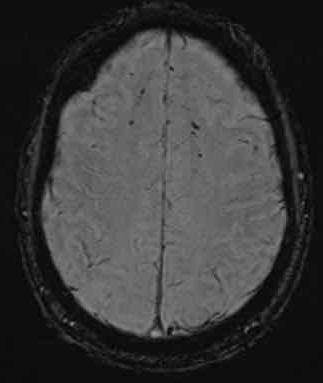

下图 一位46岁的男子骑摩托车时受伤。

瞳孔无反应性,瞳孔扩张。

CT:额叶点状出血。

继续做核磁共振成像

弥漫性轴索损伤(DAI)MRI表现

- 累及皮质下区、胼胝体、右侧丘脑和壳核、脑干、小脑脚和右侧小脑半球。

- 轻度全球萎缩。

MRI可准确诊断DAI,包括T2*GRE或SWI。

DAI在颅脑损伤患者MRI上的存在,更有可能导致不良的功能结局。